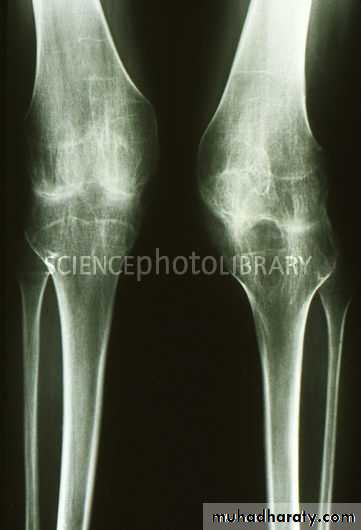

Hemophilia & bleeding disrorder :

Repeated haemorrahge in to the joints result in soft tissue swelling , erosions and cyst in subchondral bone , the epiphysis may enlarge & fuse prematurely .

Osteoarthritis :

OA is the commonest form of arthritis , resulting from wear & teat of the articular cartilage .Features seen in OA :

1.joint space narrowing. 2. Osteophytes. 3. Subchondral sclerosis . 4. Subchondral cysts.

OA

RA

1.joint space narrowing maximal at weight- bearing site.

2. erosions don’t occur but crumbling of the joint surface may mimic erosions.

3.subchindral cyst & sclerosis may be seen.

4.sclerosis is a prominent feature.

5. no osteoporosis.

1.joint space narrowing uniform.2. Erosions a characteristic feature.

3. not a feature but erosion enface may mimic cysts.

4. sclerosis is not a feature unless there is secondary OA.

5. osteoporosis often present .